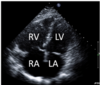

21.2 A 69-year-old woman has a recent onset of dyspnoea and undergoes a right heart

catheterisation, with results displayed below. Her pulmonary capillary wedge pressure is 10

mmHg. The most likely diagnosis is

A

Assuming pathology is pre-lung (normal PCWP).

? Pulmonary stenosis

Hol: what about PE? More consistent w history (although why do right heart cath and no CTPA?)